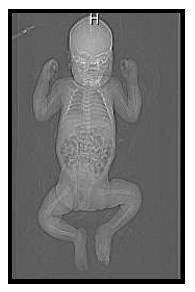

Nejmenší pacient vyšetřený na našem oddělení.

Třítýdenní holčička měřící 40cm a vážící pouze 1,6kg. Byla

přivezena z neonatologické kliniky a vyšetřena pro podezření na

zhoubný novotvar měkké tkáně dolní končetiny. PET prokázal zvýšenou

aktivitu v plosce levé nohy.